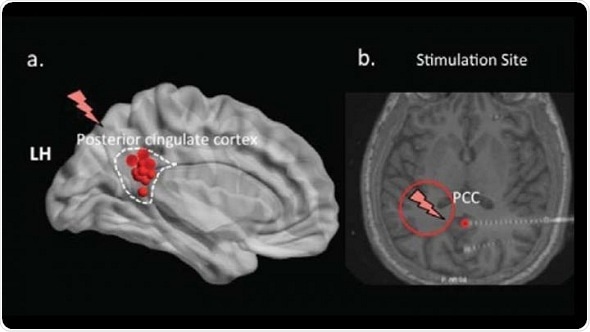

Vaidehi Natu and colleagues at the University of Texas Southwestern Medical Center stimulated the posterior cingulate cortex, a brain region involved in memory, using electrodes inserted into the brains of epilepsy patients to treat seizures. The participants were shown a list of words, distracted, and then asked to recall the words.

Natu’s team discovered that stimulating the cingulate cortex reduced the number of recalled words and modified hippocampal brain waves compared to no stimulation. This establishes a direct role for the cingulate cortex in memory encoding and demonstrates that memories can be manipulated via deep brain stimulation, which has implications for the treatment of memory disorders.